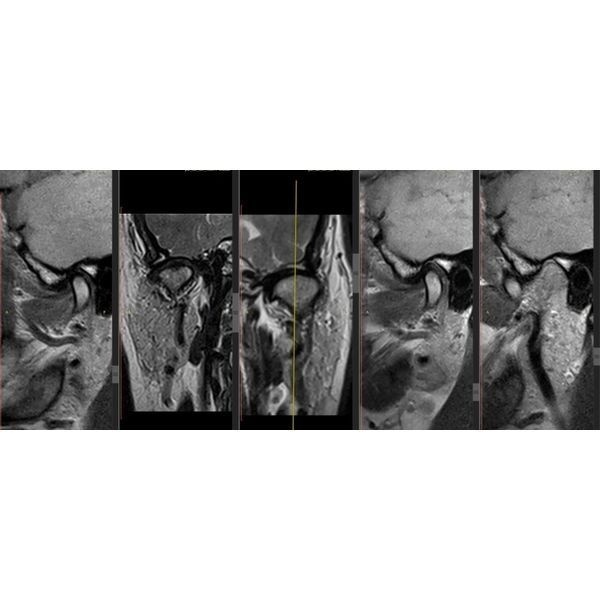

По результатам магнитно-резонансной томографии (МРТ) правого сустава:

- полное вентральное смещение суставного диска с редукцией — диск смещён вперёд, но при открытии рта суставная головка «запрыгивает» на диск;

- дистрофические изменения диска — диск начал терять эластичность и нормальную структуру;

- тенденция к перфорации промежуточной зоны диска — в средней части диска появляется риск возникновения сквозного отверстия;

- дорзальный тип установки головки мыщелкового отростка нижней челюсти — головка нижней челюсти стоит слишком далеко назад (дорзально) в суставной ямке (неправильное положение);

- остеоартроз ВНЧС 2-й степени по Kellgren — начальные дегенеративные изменения сустава.